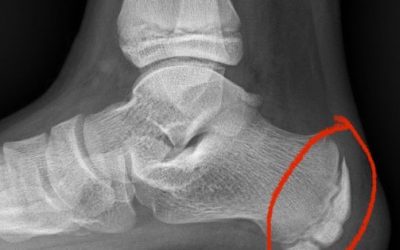

¿Cuál es el mejor tratamiento para el dolor de talón?

Hay tres tratamientos que van a cambiar la evolución del dolor de tu talón. Son muy efectivos, pero siempre que se haga previamente un buen diagnóstico y se haga una buena estrategia de tratamiento. Infiltraciones de corticoide Indicadas para fascias inflamadas , sólo...